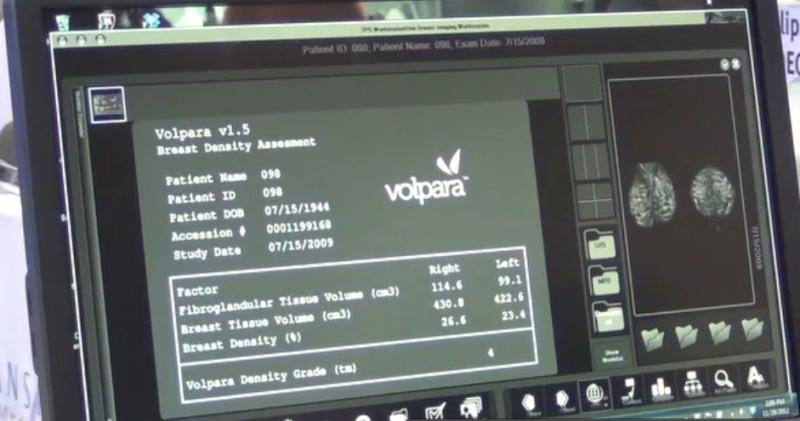

Breast density may be one of the strongest predictors of the failure of mammography to detect cancer, according to an educational session presented at the 2014 Radiological Society of North America (RSNA) conference in December. The topic of breast density was a prominent one at the meeting, and many healthcare providers are beginning to look beyond just using traditional mammography to assess whether or not a woman has breast cancer. The push for additional screening is becoming prevalent, and many states are enacting laws that require women to be notified if they have dense breast tissue and what that means in terms of the ability to accurately find cancer.

Multiple studies and products were presented at the 2014 Radiological Society of North America (RSNA) conference in December about emerging technologies in breast imaging, with a focus on how they will affect women who have dense breasts. Most researchers have been comparing the utility of mammography screening versus tomosynthesis.